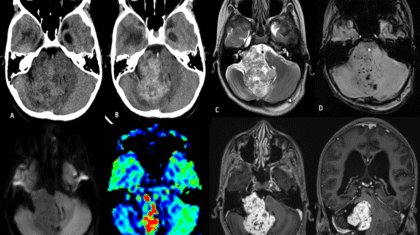

11 year old female child presented with history of right sided hearing loss, vertigo and imbalance since 6 months, right facial numbness, facial asymmetry and difficulty swallowing since 3 months, headache and vomiting since 1 month duration.